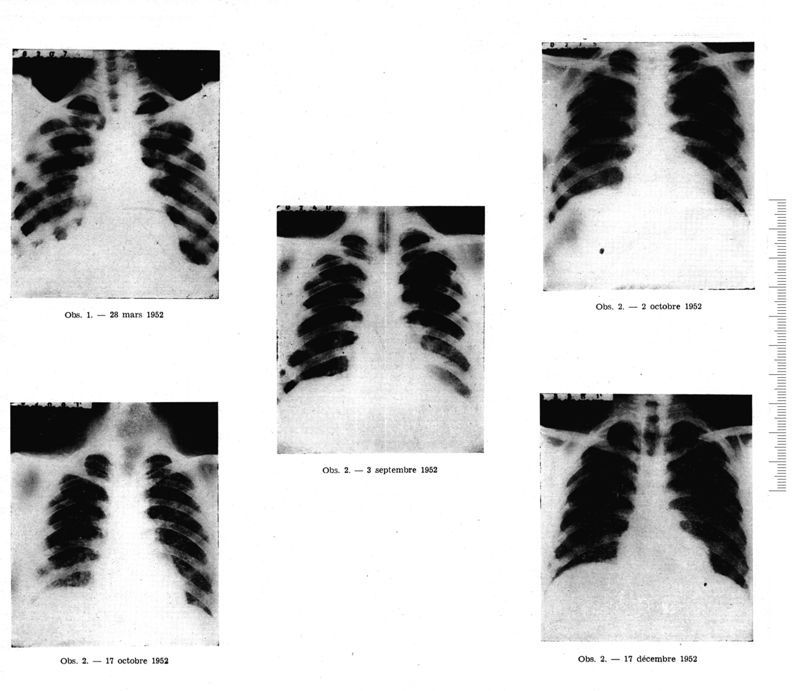

Médecine tropicale : Revue du corps de santé colonial

. - Marseille : Ecole d'application du service de santé des troupes coloniales, 1954.